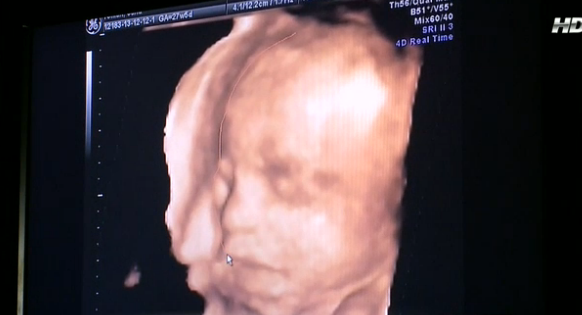

Oana Roman este foarte fercită pentru că a reuşit să îşi vadă fetiţa, după ce a făcut o ecografie 4D.

''Are nasul lui Marius. O să fie energică. O să semene cu mine'', a fost prima reacţie a Oanei. ''Am emoţii deja. Abia aştept să o ţin în braţe. Are nasul meu şi buze cărnoase ca ale mele. Dacă acum ar fi să mai zic ce aş vrea, mi-aş dori fetiţă. Nu aş mai renunţa la această idee'', a povestit emoţionat iubitul Oanei.